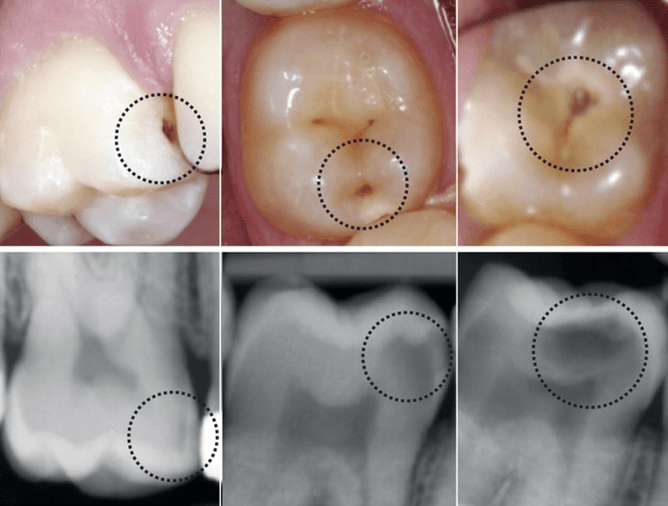

Picture above showing dental decay seen in the mouth and then the same dental decay on the dental radiograph.